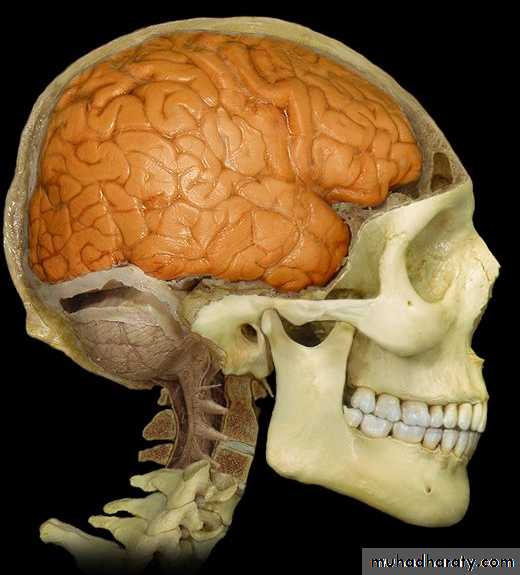

Lobes of Cerebral Hemisphere

Five lobes

Frontal lobe

Parietal lobe

Temporal lobe

Occipital lobe

Insular lobe

Parietal lobeOccipital lobe